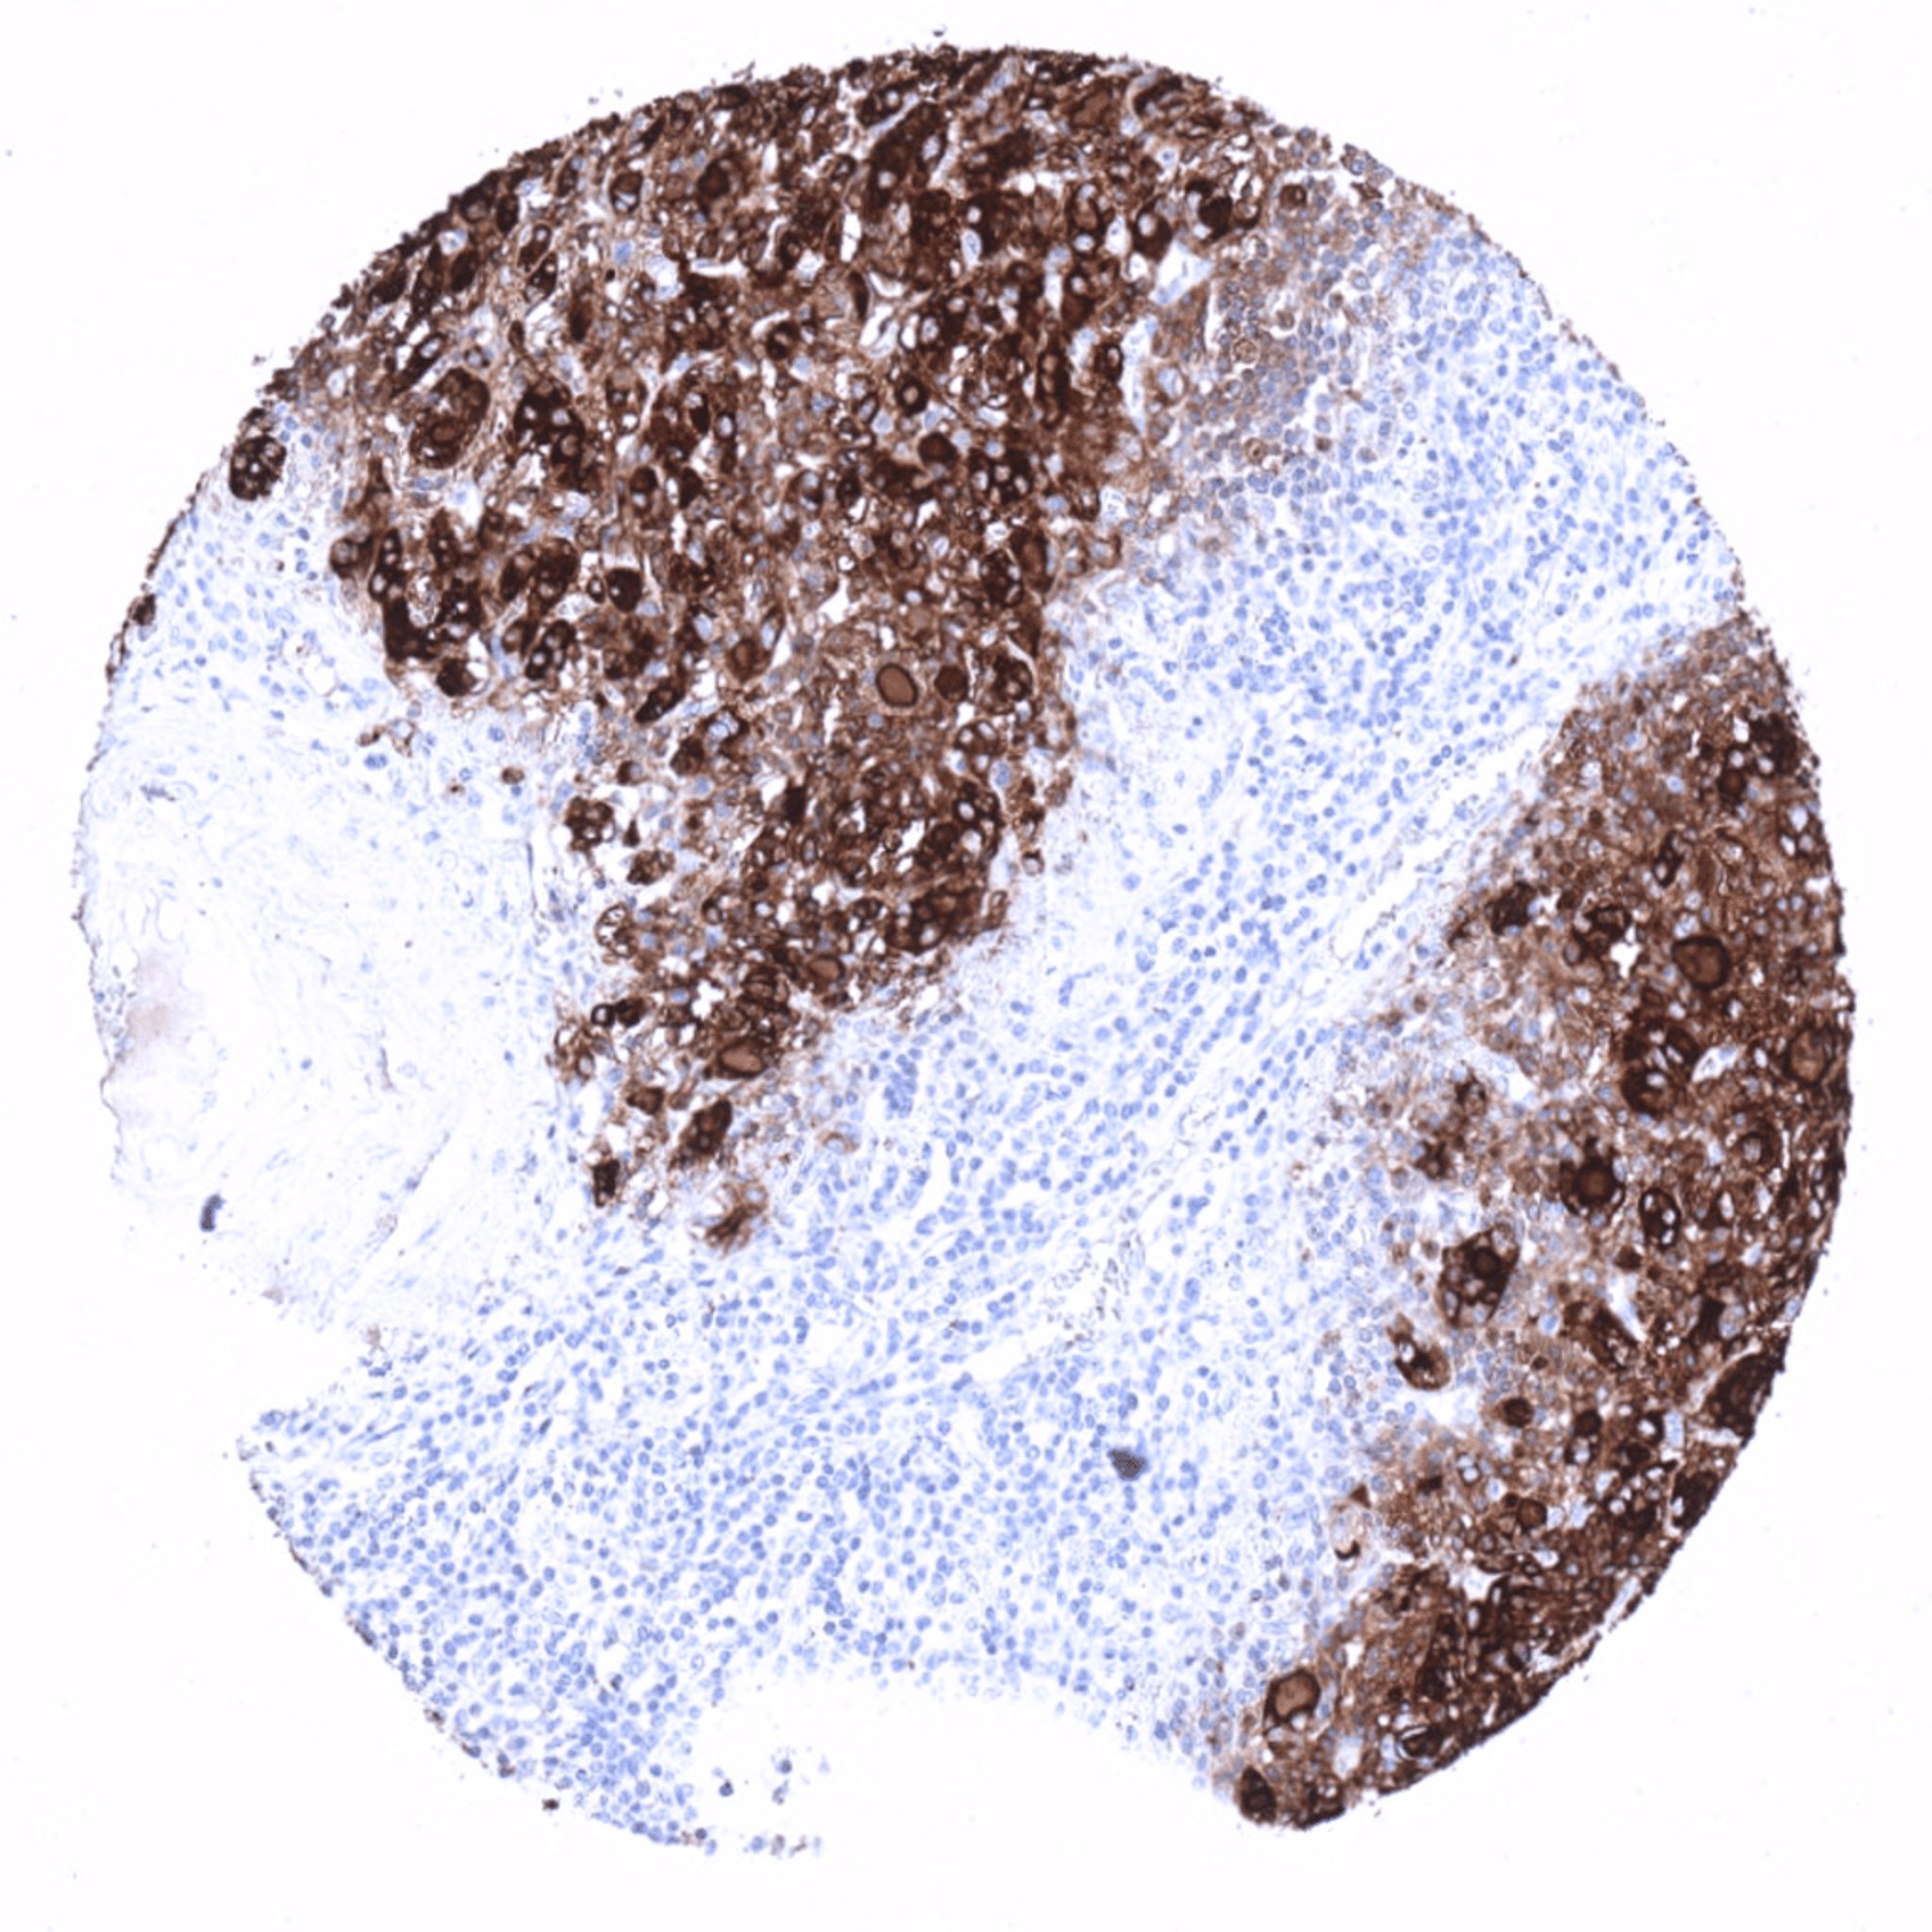

Thyroglobulin positive medullary thyroid cancer adjacent to normal thyroid tissue.